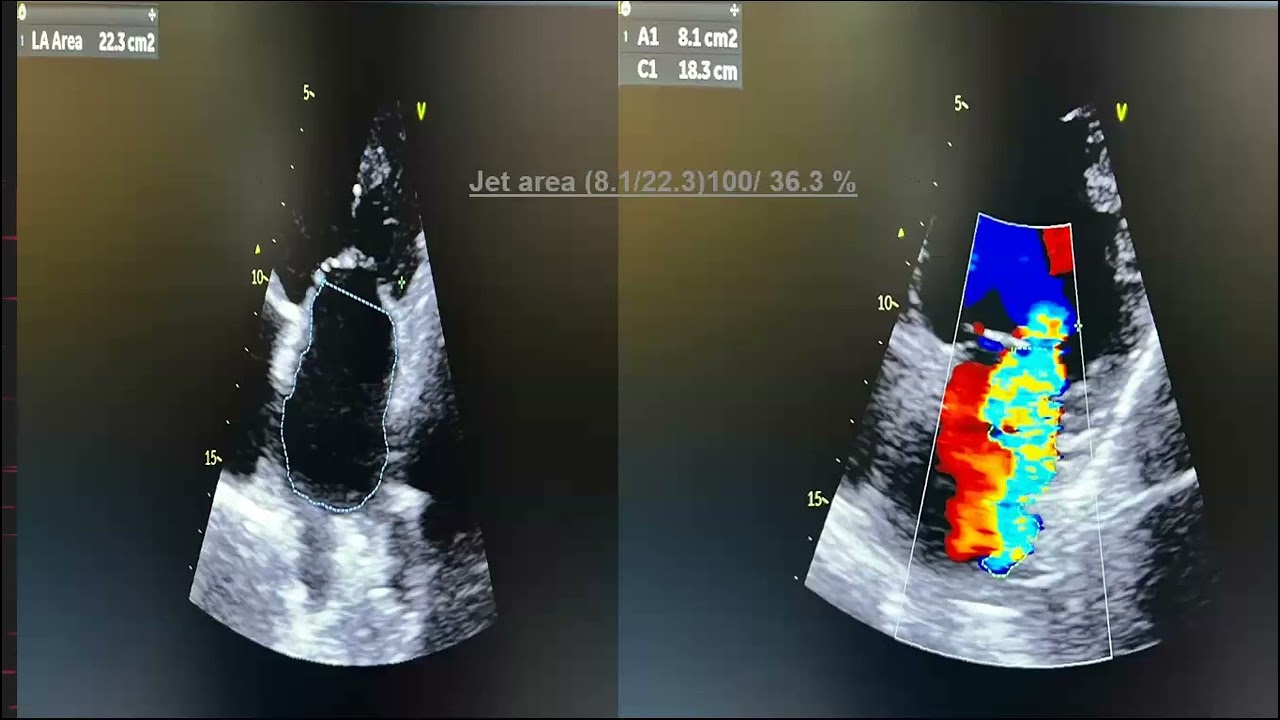

Скачать или смотреть Echo conference 25/2/2026- Dr. Mikhael Mamdouh - dilated cardiomyopathy with LV thrombus

Echo conference 25/2/2026- Dr. Mikhael Mamdouh - dilated cardiomyopathy with LV thrombus